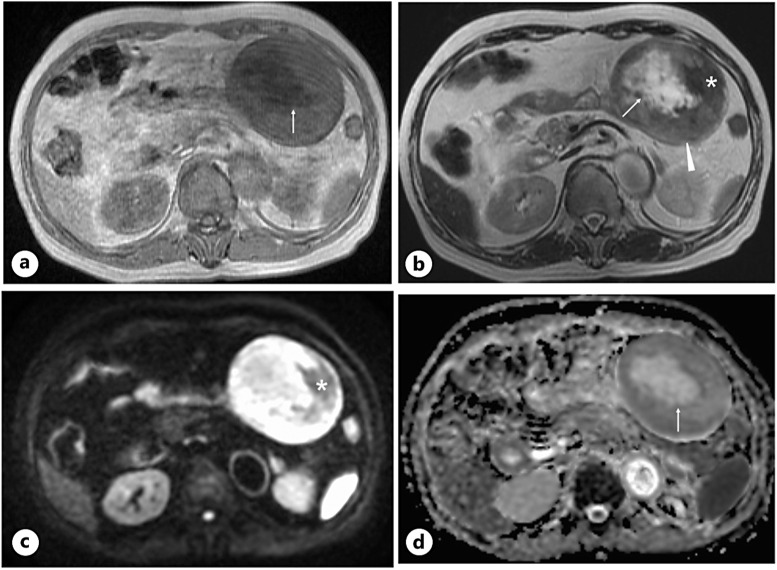

Case presentation: An 80-year-old woman was referred to our hospital due to the detection of an abdominal mass on ultrasound (US). CT showed a well-demarcated oval mass, 11 cm in size, with a central low-density area. US showed high internal echoes and enhanced posterior echoes. Magnetic resonance imaging (MRI) showed the low-density area on CT to be hypo-intense on T1-weighted images and hyper-intense on T2-weighted images. MRI further showed the central part of the tumor to be hyper-intense both on diffusion-weighted images and apparent diffusion coefficient images. Under the tentative diagnosis of a gastrointestinal stromal tumor with central necrosis, the patient underwent tumor resection, revealing the tumor to be a jejunal submucosal tumor. Pathological study showed collagen fibers with heterogeneous density and sparse proliferation of spindle cells. The center of the tumor had marked edema in addition to sparse collagen fibers. Immunostaining showed that the atypical cells were diffusely positive for β catenin and negative for S100 protein, desmin, and DOG1, leading to the diagnosis of desmoid tumor (DT).